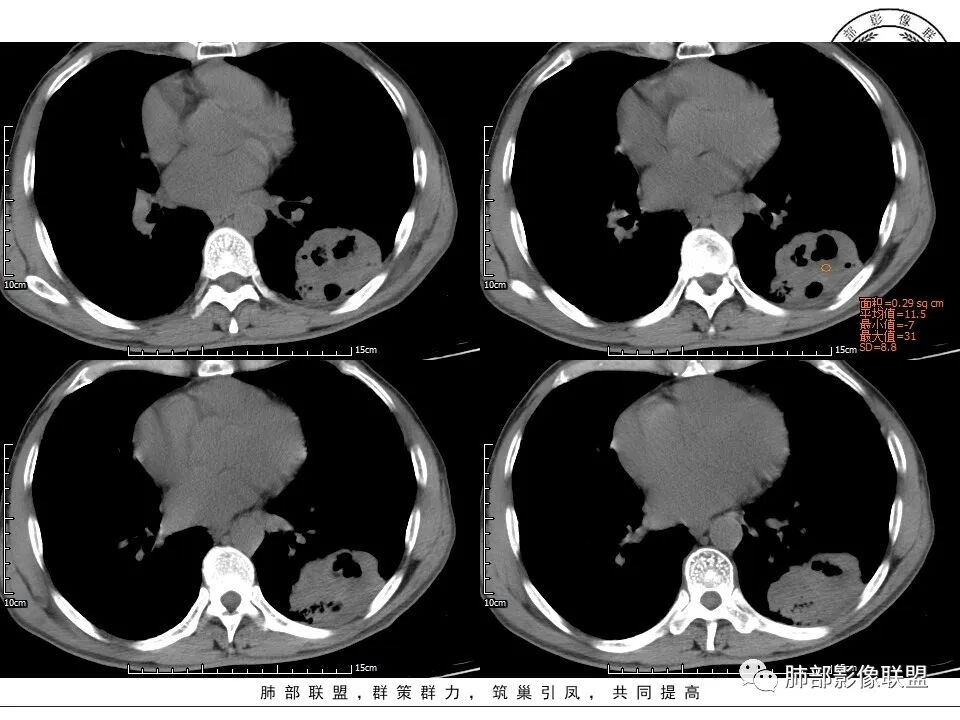

1、老年男性,肺气肿背景,咳嗽胸闷一个月,血象不高,C反应蛋白无明显升高,无发热。

2、左肺下叶近胸膜下较大肿块,土豆样外形,边缘清楚,膨隆分叶,未见明显渗出;病灶内部多坏死及空洞,似鬼脸征,坏死边界不清;增强扫描轻度不均匀环形强化;近端支气管似有阻塞截断。肺门纵隔未见肿大淋巴结。

3、综上所述,考虑恶性,鳞癌可能。

患者中老年男性,咳嗽、胸闷1月余。查肝肾功能、血糖、血脂、心肌酶异常不明显;血常规提示血象不高,轻度贫血;血沉、C反应蛋白、降钙素原无明显升高。胸部CT:肺气肿背景,左肺下叶胸膜下不规则肿块,边缘光滑,边界清楚,见浅分叶,其内见多发分隔空洞及坏死,似鬼脸征,支气管显示欠清,增强不均匀强化。右肺下叶胸膜下间质纤维化改变。综合肿块考虑恶性病变,鳞癌或肉瘤样癌可能大,鉴别隐球菌。

胸CT:肺气肿背景,双肺下叶背侧蜂窝影,左肺下叶肿块影,位于交界地带,边缘清,膨隆、分叶,内有多发厚壁空洞(重叠在蜂窝背景上,不敢确定真实性),洞壁光滑,内有多灶性坏死,支气管在肿物边缘截断,胸膜局部增厚,中度强化。考虑:恶性肿瘤,鳞?肉瘤?鉴别TB、隐球等。